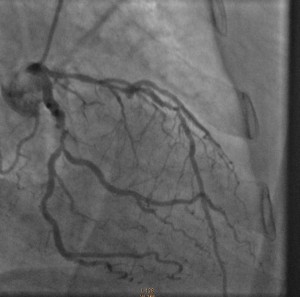

Cardiac catheterization revealed 80% to 90% proximal and mid-stenoses in the left anterior descending (LAD) artery, the left circumflex (LCX) artery, and the right coronary artery (RCA). TIMI 3 flow was noted throughout. The LAD and LCX arteries are shown in the left image below; the RCA is shown on the right.